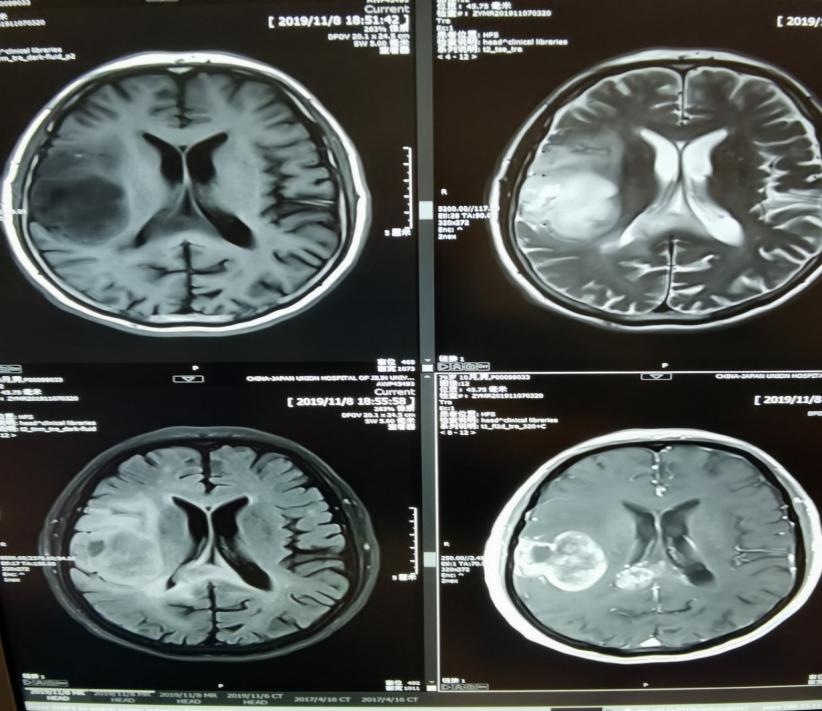

脑肿瘤

急性腔隙性脑梗死